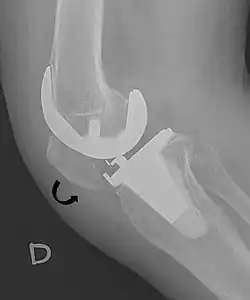

- ^ Melloni, Pietro; Veintemillas, Maite; Marin, Anna; Valls, Rafael (2013). "Imaging Patellar Complications After Knee Arthroplasty". Arthroplasty - Update. doi:10.5772/53666. ISBN 978-953-51-0995-2. (CC-BY-3.0)